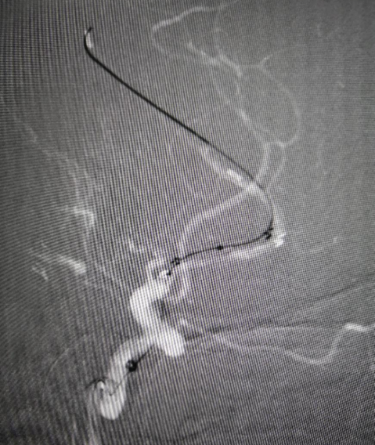

赛诺球囊扩张(1.5 mm×15 mm)

赛诺球囊扩张后狭窄有所改善但管壁不光滑

药物球囊扩张(2.0 mm×20 mm)

药物球囊扩张后

药物球囊扩张后10分钟狭窄明显改善且血管壁较光滑

扩张前带涂层的球囊(左图)与扩张后释放完涂层的球囊(右图)